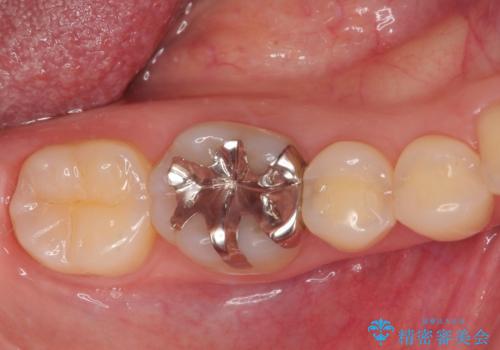

銀歯の下の虫歯|オールセラミッククラウン

担当医 河野豊嘉

奥歯に虫歯があると言われた セラミッククラウンでキレイで長持ちする歯へ

担当医 榊原康平